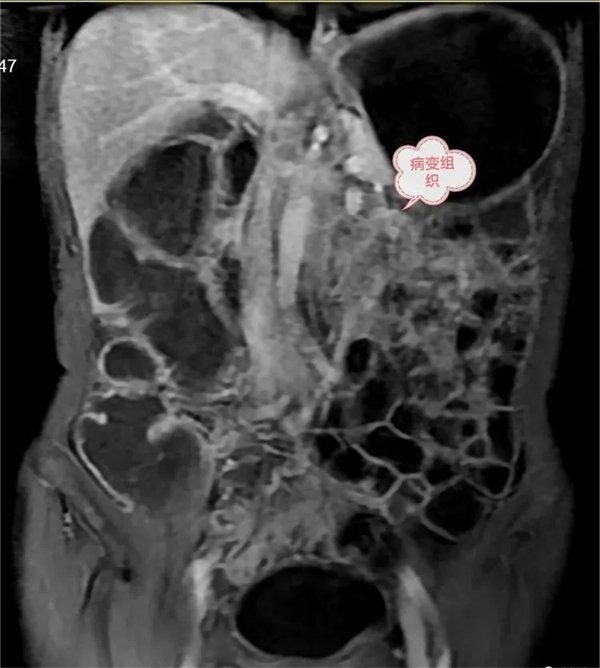

圖3:延遲期,顯示腸系膜根部病變逐漸輕度強化。胃,結腸充盈顯示良好,腸壁強化,未見異常。

圖4:磁共振功能成像清晰顯示病變DWI呈明顯高信號,ADC圖呈低信號,腹膜后多發小結節灶。